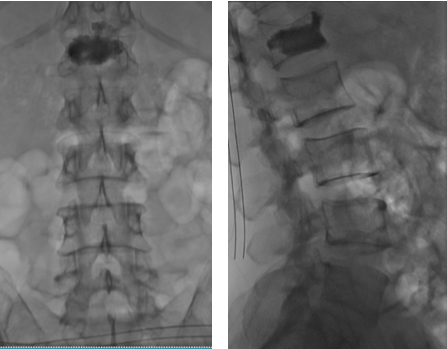

Tại Khoa Ngoại Chấn Thương, bệnh nhân được chụp CLVT, MRI cột sống ngực lưng, kết quả: Vỡ xẹp thân đốt sống L1 và có phù mô xương xốp. Êkip bác sĩ Ngoại CTCH và DSA tiến hành hội chẩn và tư vấn gia đình hướng điều trị bằng phương pháp bơm xi măng sinh học.

Hình chụp MRI cột sống thấy xẹp đốt sống L1 có phù mô xương xốp